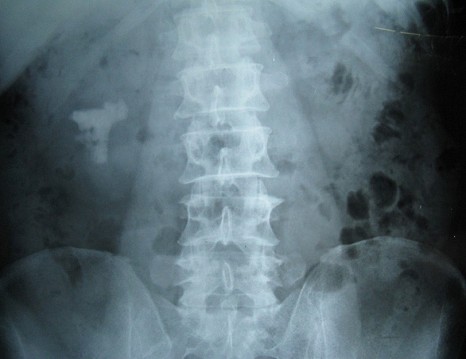

患者鐘某主因“右側(cè)腰部間斷疼痛20余年加重3個(gè)月”入院。如下圖圖1、圖2和圖3所見(jiàn)具備兩個(gè)特點(diǎn):一、結(jié)石復(fù)雜,除主體位于腎盂和中下大盞外,多個(gè)中下小盞內(nèi)還有多發(fā)結(jié)石;二、沒(méi)有腎積水,腎盞杯口不大。

1 術(shù)前KUB平片可以清晰地看到右腎復(fù)雜性鑄型結(jié)石